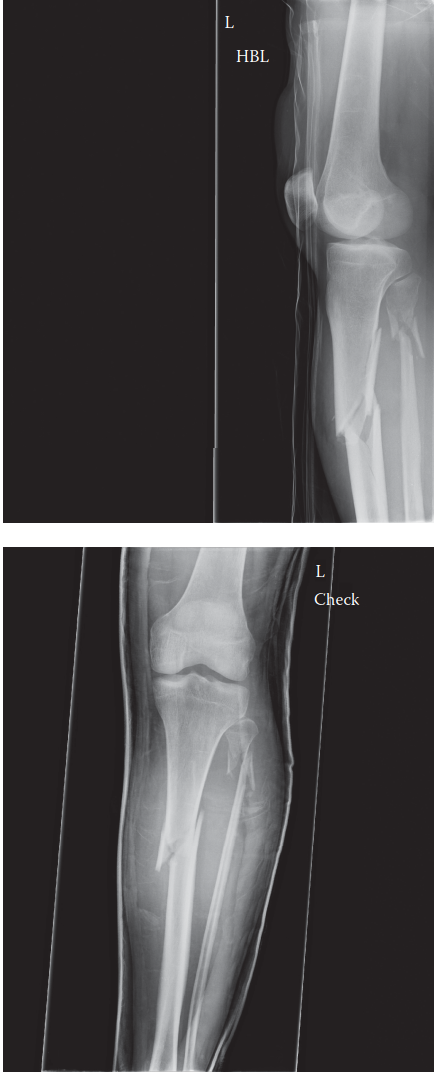

Tibial Fracture: Proximal Deformity Answers for Surgeons

. Can you describe the radiographs? These are AP and lateral radiographs of the left tibia and fibula showing…